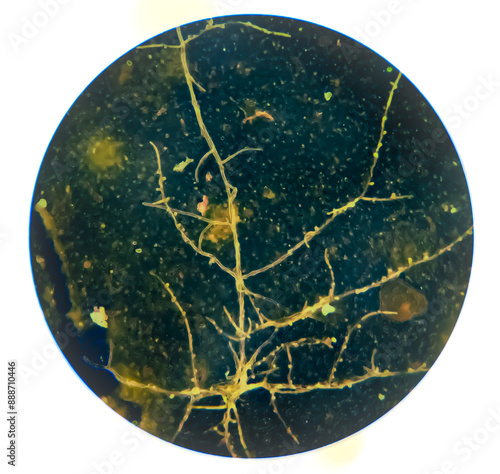

Mikrofotografi - Plakater, Poster, Billeder på lærred